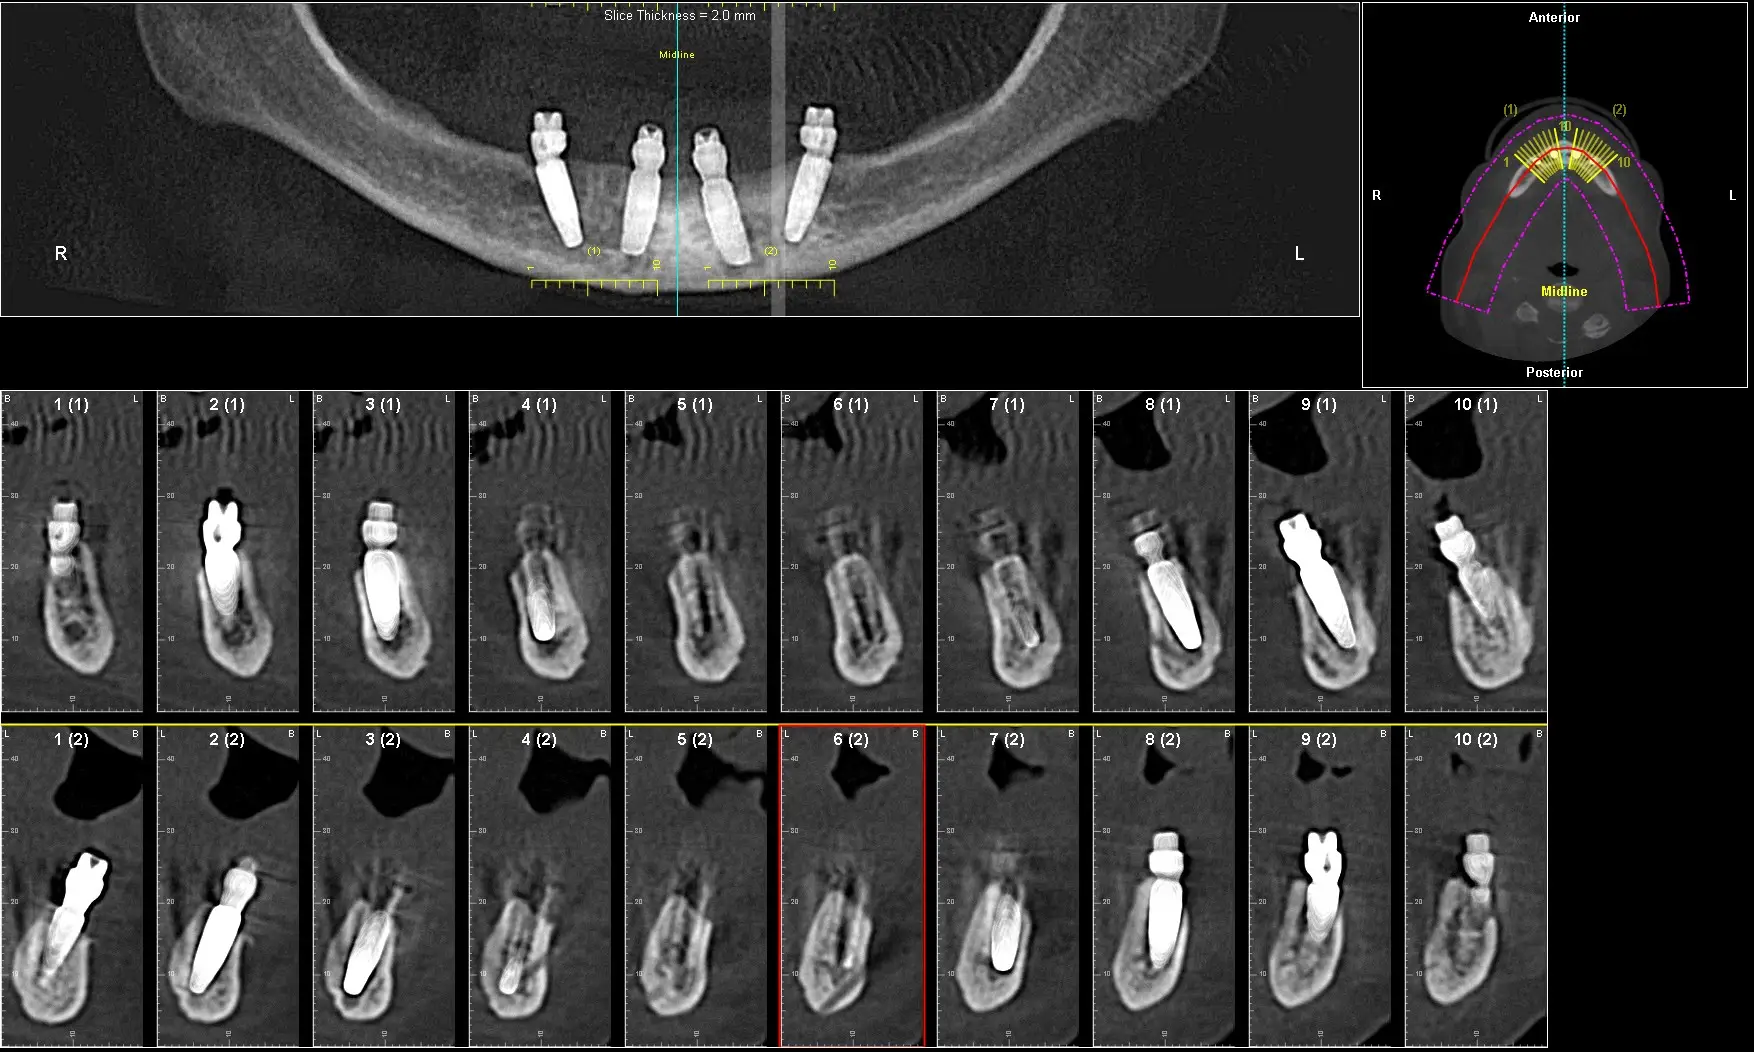

Clinical Case Example

Documented case of Ana, a patient presenting with severe bone loss and failed implants. She was treated by our faculty member, Dr. Jay Neugarten, during the ZAGA Course as part of a live surgical demonstration for course participants. Treatment involved quad zygomatic implants and one pterygoid implant to improve stability. Using the ZAGA Approach, we were able to successfully rehabilitate the case despite the previous implant failures and deliver an immediate prosthesis on the same day as surgery. This case represents part of the clinical education and knowledge participants gain during the ZAGA course.